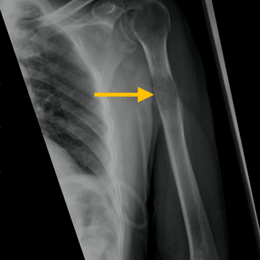

Radiographic imaging is used to help form a diagnosis of Myeloma. These include X-Ray, MRI, CT and Bone Scans

An example of a Myeloma X-ray is shown. Myeloma may present as a diffuse osteoporosis with the bones throughout the body looking very thin on X-rays.